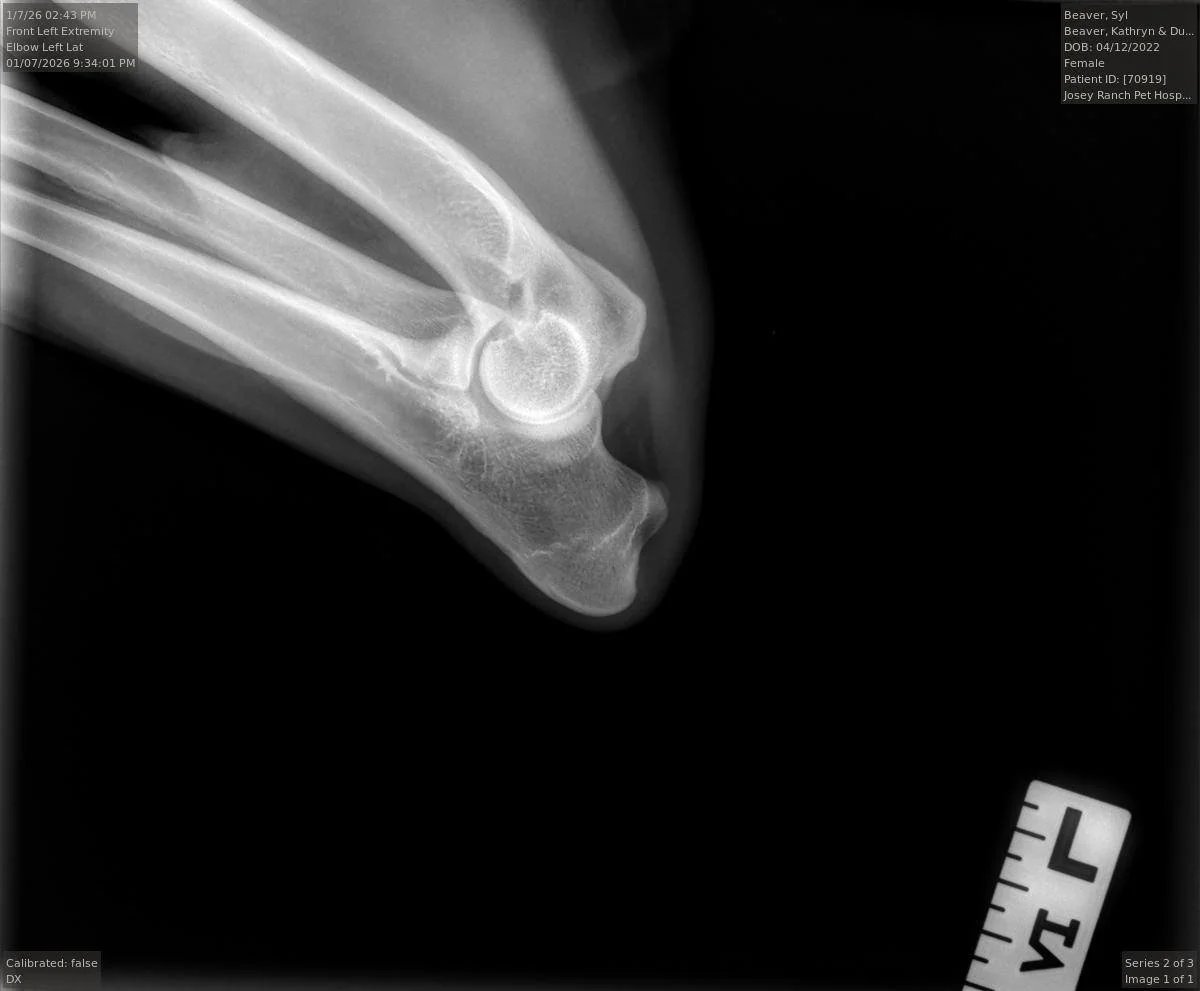

Syl’s left elbow x-ray, taken at 2 years and 9 months old, intact.

Syl’s OFA Certificate: Elbows Normal